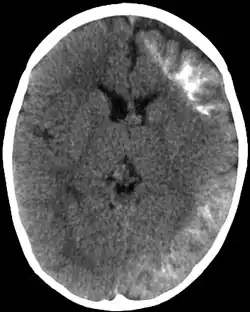

CT scan of Sturge-Weber syndrome | |

Sturge–Weber is an embryonal developmental anomaly resulting from errors in mesodermal and ectodermal development. Unlike other neurocutaneous disorders (phakomatoses), Sturge–Weber occurs sporadically (i.e., does not have a hereditary cause). It is caused by a mosaic, somatic activating mutation occurring in the GNAQ gene.[2] Imaging findings may include tram track calcifications on CT, pial angiomatosis, and hemicerebral atrophy.[3]

CT and MRI are most often used to identify intracranial abnormalities. When a child is born with a facial cutaneous vascular malformation covering a portion of the upper or the lower eyelids, imaging should be performed to screen for intracranial leptomeningeal angiomatosis. The haemangioma present on the surface of the brain is in the vast majority of cases on the same side as the birth mark and gradually results in calcification of the underlying brain and atrophy of the affected region.[5]